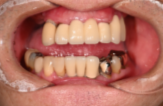

インプラントの症例紹介①

Before

After

主訴

歯が抜けてしまった

治療内容

上顎に対するインプラント治療を行った。

治療費

2,046,000円(税込)

治療期間

1か月

通院回数

3回

※治療回数は1回

想定されたリスク

※最終的な歯が入るまでは仮歯の装着が必要でした。

One Dayインプラントは、手術当日(※術前の検査、術後の経過観察が必要になる場合があります)に仮歯が入るため、その日からしっかり噛めます。入れ歯の必要がなく、治療中の煩わしさを軽減できます。